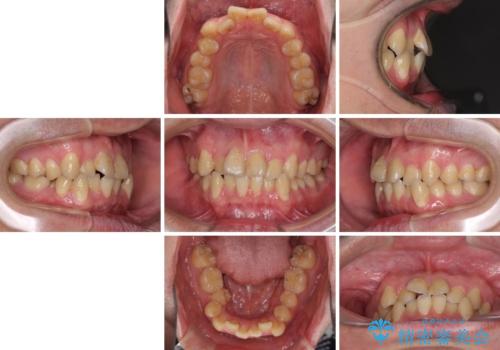

- 上下のデコボコと前歯のクロスバイトを改善したいとのことで来院された患者様です。

マウスピース矯正での自己管理には自信がないとのことで、ワイヤー装置による矯正治療を行うこととしました。

デコボコの程度は強かったのですが、口元の突出感はなかったため、非抜歯矯正としました。